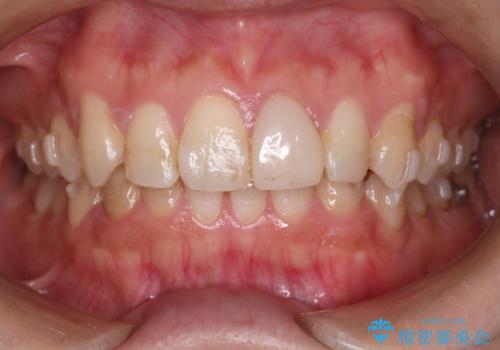

- 前歯のがたつきと口元を下げたいとのことで来院されました。

骨格的に左右差があるので正中を合わせることと抜歯矯正での口元改善は難しいことを説明させていただきました。

患者様に理解していただいた上で、インビザラインにてIPR(歯と歯の間を削る処置)を行いながら前歯のがたつきを整える治療計画を立てました。

インビザラインにて治療を行うことで、前歯のがたつきが改善されました。

左上1番目の前歯はセラミックをご希望されたので、セラミックにて被せ物の治療を行いました。

とても綺麗な前歯になりました。